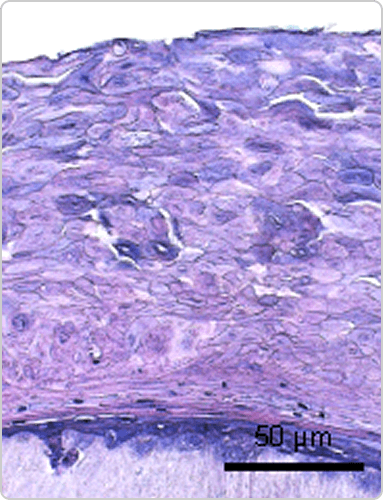

인체화 피부 모델(RHS) 평가

• TNF-α / IL-4 / IL-13으로 유도된 AD 표피 비후 모델에서 BSP011 처리 시 표피 비후가 정상 대조군 수준으로 회복

• Contorl

• AD cocktail

• AD cocktail + Dup*****

• AD cocktail + BSP011